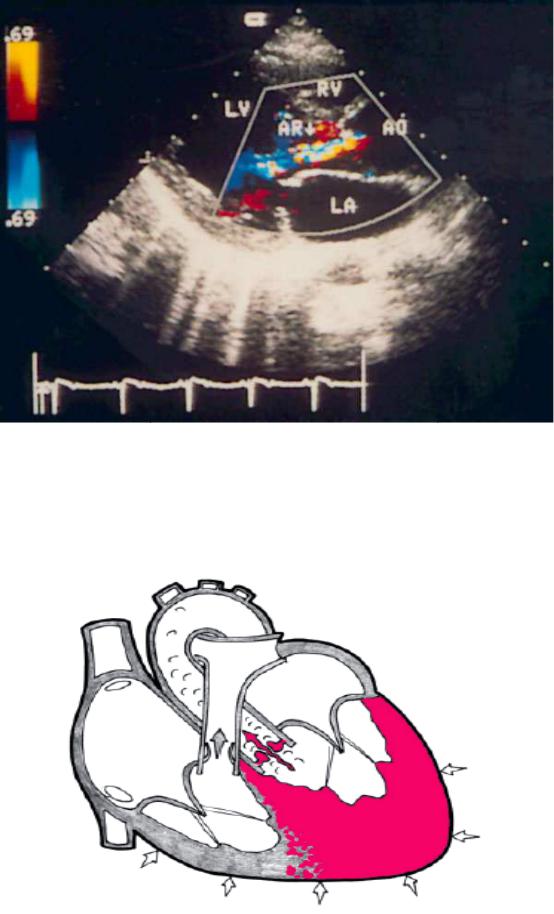

Fig.5.Aortic incompetence

Fig.6. Aortic regurgitation, the severity — from small to moderat e. Color Doppler study of the position of the parasternal long axis of left ventricle. Motley regulatorului flow begins at the level of closin g of the flaps of the aortic valve. LV — left ventricle, LA — left atrium, RV — right ventricle, Ao — ascending aorta, AR — aortic regurgitation.